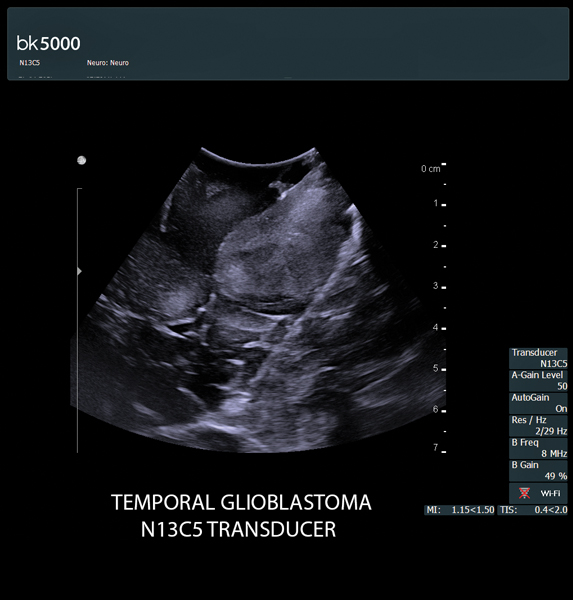

Ultrasound can improve neurosurgical procedures by helping you navigate and identify lesions and anatomical structures in real-time. This is particularly important as the data obtained from a preoperative CT or MRI scan can be outdated at the time of surgery. The bk5000 neurosurgical system provides the highest quality images that allow you to clearly see the margins of a lesion and to determine the best course of action. Using advanced graphics processing technology, this powerful system provides immediate, auto-optimized images that allow you to see the information you need, faster.

Transducers designed for Neurosurgery

The specialized, high-resolution, sterilizable neurosurgery transducers enable you to obtain detailed images of the brain and spinal cord. They have a convenient Smart™ button that lets you activate the transducer, then freeze, store or print the images at the press of a button. Disposable, easy-to-use needle guides assist with targeting lesions.